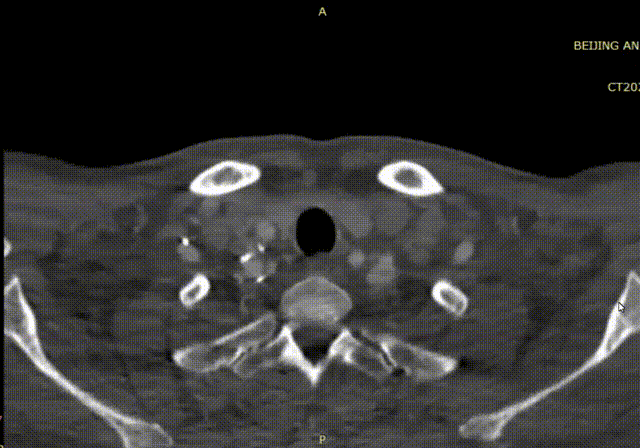

王盛教授分享了首都医科大学附属北京安贞医院的一例极具代表性的临床病例,并引导了现场专家对于颈动脉狭窄三种主流术式选择策略的深度探讨。患者为43岁男性,无症状,体检发现右侧颈动脉重度狭窄(70-80%),影像学(超声、CTA)提示为“次全闭塞”,病变长度约24mm。患者相对年轻且合并多种心血管高危因素,这使得术式选择充满了博弈,是选择经典的金标准CEA,还是微创的CAS,抑或新兴的TCAR?针对此病例,现场讨论嘉宾从解剖条件、全身状况、斑块性质三个维度进行了深入剖析。

波科支架怎么样波科@CEC2025|TCAR新技术手术交流会精彩荟萃_https://www.jmylbn.com_新闻资讯_第8张

波科支架怎么样波科@CEC2025|TCAR新技术手术交流会精彩荟萃_https://www.jmylbn.com_新闻资讯_第9张

1、解剖适应性

郭大乔教授、刘建林教授、吴巍巍教授一致认为,该患者颈总动脉直径、病变位置及血管入路条件非常适合进行TCAR。郭大乔教授补充道,若病变长且狭窄,可选择CEA。

2、术式比较

刘建林教授指出,若患者心肺功能良好,CEA同样是合理且有效的选择。陈忠教授提到,鉴于病变为“次全闭塞”,若行经股动脉的CAS,在通过病变放置保护伞时存在较高的栓塞风险。因此,决策天平在CEA与TCAR之间倾斜。

3、斑块稳定性评估

史伟浩教授强调,除了解剖学,斑块性质的评估至关重要。杨轶教授建议对高危患者采用高分辨率磁共振成像或超声造影来检测斑块内的新生血管、脂质核心和钙化情况,以判断其稳定性。郭大乔教授补充称,若通过超声造影可看到新生血管,判断为不稳定斑块,一般来说,CT值< 20 Hu,血栓或大的脂质坏死核心成份可能大,>40 Hu则纤维成份较多,>100 Hu则倾向于较稳定的斑块成份,钙化斑块的CT值会更高。针对该病例行TCAR较CEA更安全,因为TCAR逆流脱落血栓捕捉率高。

该病例对CAS、CEA与TCAR均无绝对禁忌。评估斑块稳定性时,高分辨率核磁或造影虽有参考价值,但临床表现,如术前有脑梗或TIA史,即可基本判定为不稳定斑块。本例病变属“次全闭塞”,经股动脉CAS在通过病变时存在碎屑脱落风险。就现有数据比较,TCAR的临床证据颇具优势,其围术期卒中发生率低于CAS,颅神经损伤率又低于CEA。因此在TCAR与CEA均适用时,优先选择TCAR;若无TCAR条件,CEA是合理替代,而CAS风险较高,可作为后续选择。总体而言,在传统优选CEA的基础上,如今TCAR提供了一个非常适宜的新选择。